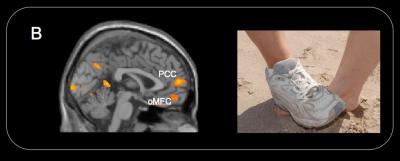

While undergoing fMRI scans, children where shown animations using three photographs of two people whose right hands or right feet only were visible.

The photographs showed people in pain accidently caused, such as when a heavy bowl was dropped on their hands, and situations in which the people were hurt, such as when a person stepped intentionally on someone's foot. They were also shown pictures without pain and animations in which people helped someone alleviate pain.

The scans showed that the parts of the brain activated when adults see pain were also triggered in children.

"Consistent with previous functional MRI studies of pain empathy with adults, the perception of other people in pain in children was associated with increased hemodymamic activity in the neural circuits involved in the processing of first-hand experience of pain, including the insula, somatosensory cortex, anterior midcigulate cortex, periaqueductal gray and supplementary motor area," Decety wrote.

However, when the children saw animations of someone intentionally hurt, the regions of the brain engaged in social interaction and moral reasoning (the temporo-parietal junction, the paracigulate, orital medial frontal cortices and amygdala) also were activated.